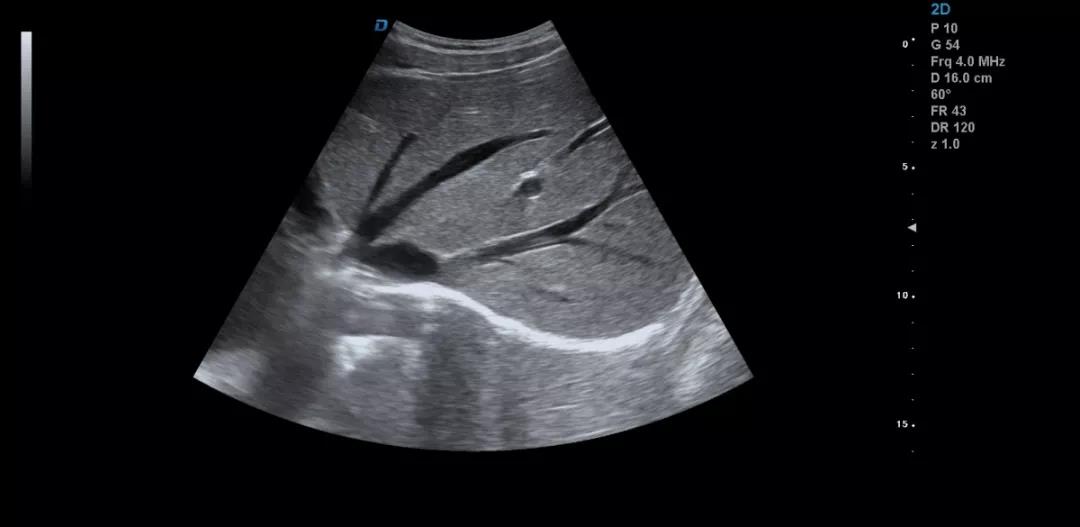

彩超機(jī)肝臟超聲的檢查方法詳解

彩超機(jī)是每個(gè)醫(yī)院常見(jiàn)的診斷設(shè)備,很多人都不陌生。可能大家認(rèn)為彩超機(jī)檢查醫(yī)生很輕松,其實(shí)不然,彩超檢查醫(yī)生也是需要精湛的操作技術(shù),專(zhuān)業(yè)的判斷才可以的。下面小編和大家一起來(lái)看下利用彩超機(jī)檢查肝臟超聲的方法。

彩超機(jī)檢查肝臟超聲方法

彩超檢查不同于其他的影像學(xué)檢查方法,彩超檢查的結(jié)果與操作者的技術(shù)、經(jīng)驗(yàn)、手法、檢查細(xì)致程度等很多因素密切相關(guān)。

眾所周知,肝臟有很多檢查死角,成為超聲檢查的盲區(qū),如肺和骨所掩蓋處,肝右前上段及右后上段的膈頂部,左外葉外側(cè)角區(qū),沿肝臟表面的肋骨下區(qū)等等部位,只有極其細(xì)致的檢查配上精巧的手法才能盡可能的顯示清楚這些部位。

如果我們能夠細(xì)致的檢查每個(gè)病人,所謂的肝臟死角能夠盡可能的探測(cè)到,肝臟的死角其實(shí)只有膈頂部,其他的部位如果能細(xì)致檢查都可以探測(cè)到。

肝左葉掃查時(shí),矚患者深吸氣,可以盡量使肝下移,更接近體表,顯示清楚,掃查至外側(cè)角肝臟消失的位置。然后探頭連續(xù)滑動(dòng),沿肋緣下斜切,矚患者深吸氣,探頭做扇形掃查,盡可能側(cè)動(dòng)探頭至與皮膚平行,肝臟的絕大部分病變不會(huì)被遺漏。

對(duì)于肥胖體型或腹腔臟器明顯的,這種方法就不合適,可以采取肋間斜切的方法,自下而上逐個(gè)肋間連續(xù)掃查,注意不要做跳躍式掃查,這樣容易眼花也容易遺漏病變。

掃查肝臟時(shí)要配合患者的呼吸運(yùn)動(dòng),采取你動(dòng)我靜,你靜我動(dòng)的掃查方法,并最大限度的側(cè)動(dòng)探頭,最大角度的顯示肝臟。

發(fā)現(xiàn)肝臟病變時(shí)要多切面多角度掃查,可以了解病變的解剖位置并排除假陽(yáng)性。